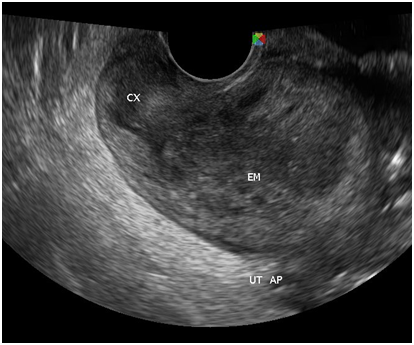

With the four‒month history of rapid abdominal enlargement and significant weight loss, the admitting impression was that of an ovarian new growth probably malignant. However, ultrasound showed only a left adnexal mass described as irregular tubular hyperechoic structure with scattered echogenic stipplings within, densely adherent to the postero‒lateral wall of the uterus, adjacent bowel loops and pelvic sidewalls, while the right ovary appeared grossly normal. Incidentally, there were multiple echogenic foci seen at inferior lobe and parenchyma of the liver, and massive anechoic free fluid was seen in the abdominopelvic cavity. A chest radiograph was also done, which showed pleural effusion on the right; findings suggestive of pulmonary tuberculosis, minimal disease. Work up for tuberculosis was done (Figures 2‒10).

Figure 7 There is a thin midline echogenicity visualized (anteroposterior view), measuring 0.3 cm suggestive of the endometrial lining.

Figure 8 The surrounding myometrium (transverse view) which is hypoechoic, irregular, with scalloping at the periphery with a mixed hyperechoic and echogenic echopattern giving it a marblelized appearance, which may be a unique variation of the usual “moth‒eaten” appearance.